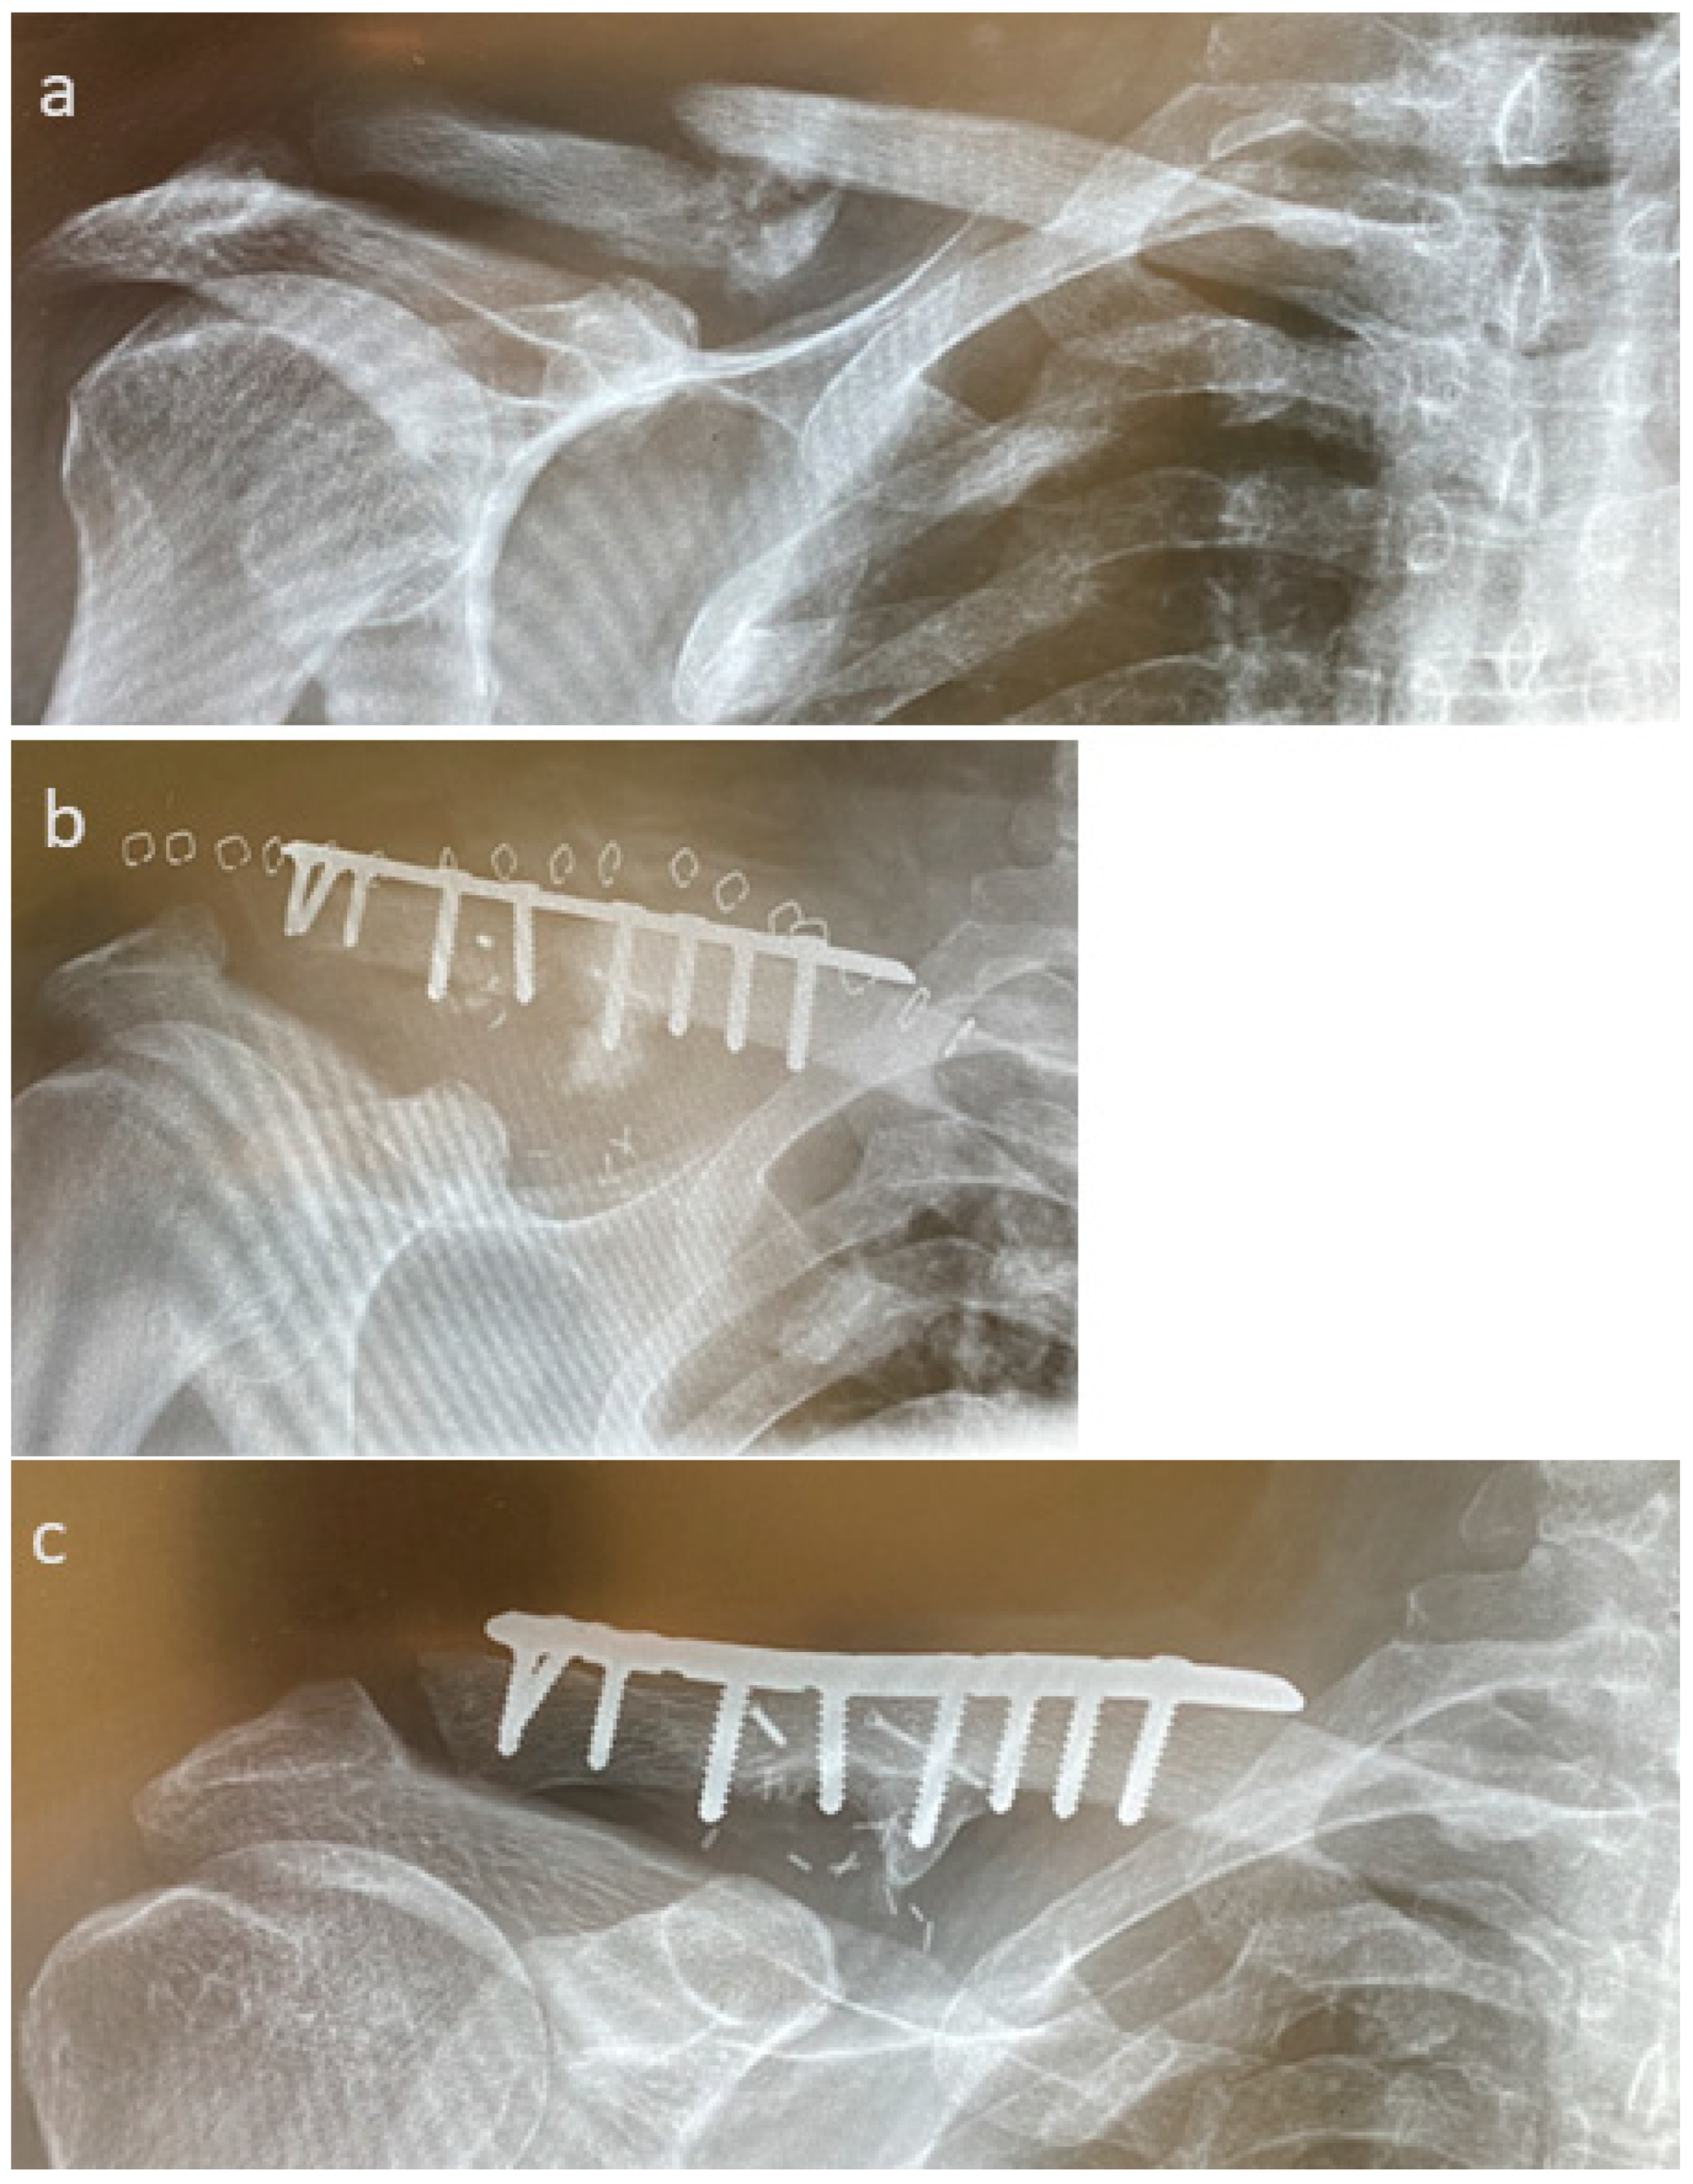

3.4. Selected Case Descriptions